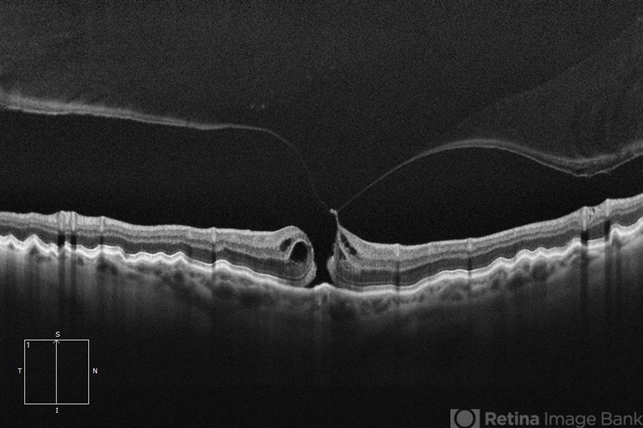

Zeiss Cirrus 6000 - Description

- HD 1 line 100x OCT showcasing a full thickness macular hole caused by vitreomacular traction on fovea. Choroidal folds can also be seen on scan.